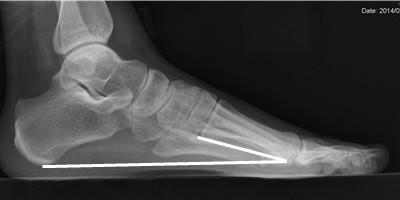

测量方法:从第1跖跗关节最低点到第1跖骨头最低点作一条直线,再从第1跖骨头最低点到跟骨最低点作一条直线,然后测量两条直线所构成的夹角

-

扁平足时前弓角减小,弓形足时相反